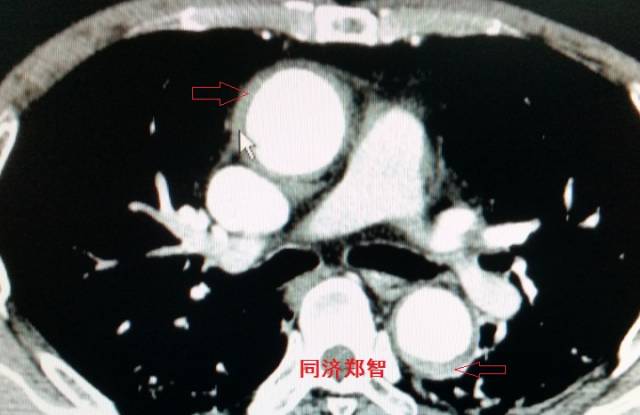

平扫CT提示降主动脉内膜片征,同时内膜片中可见一钙化点。CTA证实为B型主动脉夹层。

图17-18